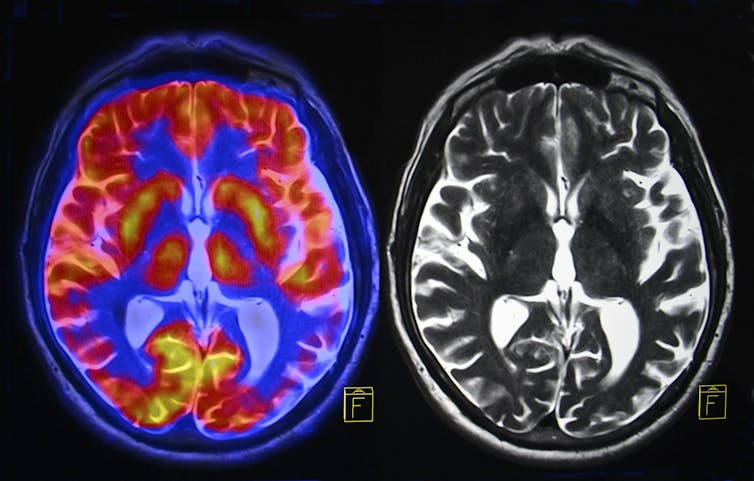

“Each of the billions of neurons in our brain is like a learning, adapting computer, with many electrically active components,” they say. “Many of these components work at a different rate depending on the ambient temperature, and are designed to work together within a narrow range of temperatures.”

A species that evolved in Africa, humans are comfortable between 20˚C and 26˚C and within 20% and 80% humidity, Sisodiya and Maslin say. Our brain is already working close to the limit of its preferred temperature range in most cases, so even small increases matter.

“When those environmental conditions move rapidly into unaccustomed ranges, as is happening with extreme temperatures and humidity related to climate change, our brain struggles to regulate our temperature and begins to malfunction.”